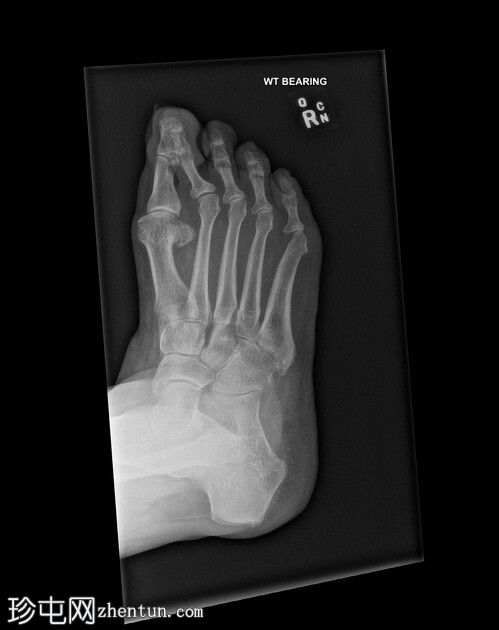

斜位片

第二趾交叉畸形,跖趾关节伸展,足趾内旋,压在相邻拇趾背侧。

第二趾内旋,压在拇趾上。患者有长期穿高跟鞋的病史。